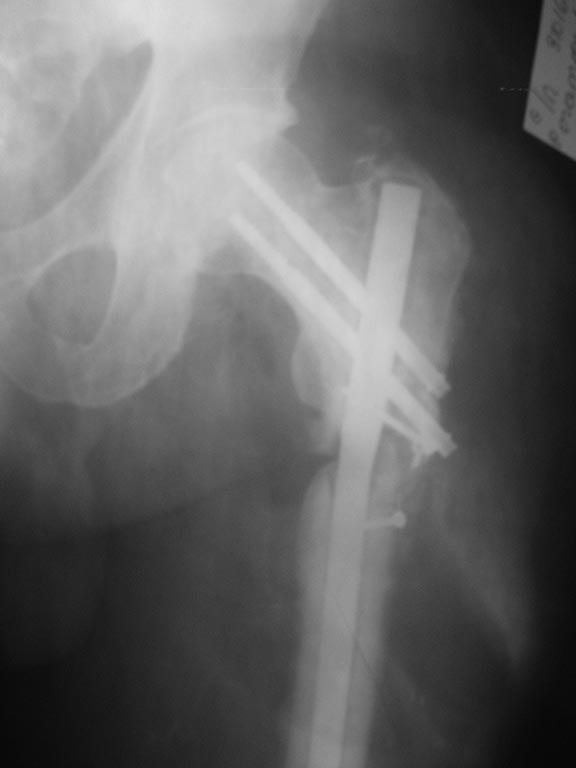

Уважаемые коллеги! Прошу совета.Пациенту 60 лет, после перелома бедренной кости прошло 11 мес, сахарный диабет тип 2 субкомпенсированный, облитерирующий атеросклероз сосудов нижних конечностей. Первично - МОС пластиной с угловой стабильностью с костной аутопластикой. Через 6 мес - перелом пластины, удаление, БИОС с костной аутопластикой. Динамизация через 8 нед после БИОС, дозированная нагрузка. Через 12 нед в связи с несращением - резекция концов отломков, дистальное переблокирование с компрессией отломков, костная аутопластика. Через 5 мес после бИОС - трансплантант исчез, несращение. Что делать дальше?

Варуса пока нет, но в дальнейшем проксимальный отдел действительно может "кивнуть", если стержень или винт не сломается ранее. У нас пока 2 варианта дальнейшего лечения:

а)удаление PFN, резекция концов и сближение, установка PFNA (ранее интраоперационно выявлен шат проксимального отломка вокруг стержня, на рентгенограмме - резорбция вокруг стержня в проксимальном отломке, поэтому стабильность отломков даже с PFNA под вопросом);

б) и радикальный - тотальное эндопротезирование с ревизионной ножкой.

Варуса пока нет

Варус между 10 и 15 градусами. На приложенной картинке зеленой линией показано, где должен быть гвоздь в центральном отломке. Угол зеленой линии с красной (нынешнее положение) и есть величина варусного смещения.

Из-за варуса нет кортикальной аппозиции по латеральной стенке, плюс сыграло негативную роль открытое вмешательство, повлекшее ухудшение кровоснабжения.

Как всегда, надо в уме держать вялотекущую инфекцию, которая после очередного остеосинтеза может манифестировать.

Так что мой выбор был бы реостеосинтез любым доступным PFN с рассверливанием. С устранением варуса, т.е. надо чуть медиализировать точку входа и направить гвоздь к латеральной стенке.

Шеечный винт/клинок получится тогда гораздо более соосно шейке бедра, ввести бы его ниже центра оси шейки, там вроде интактная кость. И буквально субхондрально.

Гвоздь благоразумнее было бы сделать с антибактериальным цементным покрытием.

Проблема внесуставная, не опухоль, сустав целый, так что эндопротез рассматривать не видно оснований.

Парафокальную остеотомию как дополнение можно обсуждать.